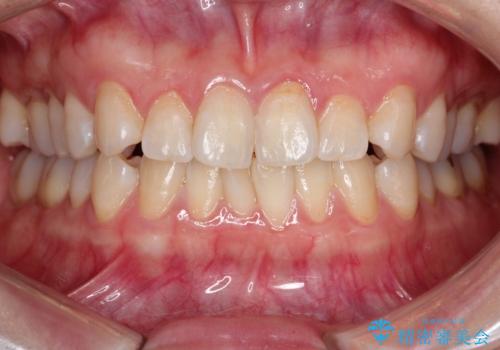

【インビザライン 】前歯の凸凹をなおしたい

- 前歯の凸凹を主訴に来院されました。

インビザライン にて治療を行い、歯並びが綺麗になったと満足していただきました。

前歯のガタガタの量が多かったため、IPR(歯のサイズを小さくするための処置)を行なって治療しました。